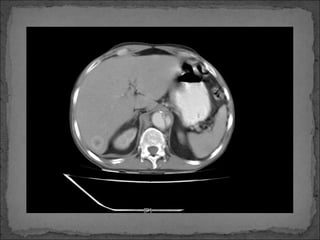

Paciente de 50 años de edad, con historia de Ca renal

diagnosticado hace 6 meses, quien súbitamente inicia

con dolor en cuadrante superior izquierdo hace 6 horas

por lo que consulta.

Facultativo le solicita una TC abdominal y luego refiere a

paciente a este centro hospitalario.

Paciente de 50años de edad, con historia de Ca renal diagnosticado hace 6 meses, quien súbitamente inicia con dolor en cuadrante superior izquierdo hace 6 horas por lo que consulta. Facultativo le solicita una TC abdominal y luego refiere a paciente a este centro hospitalario.